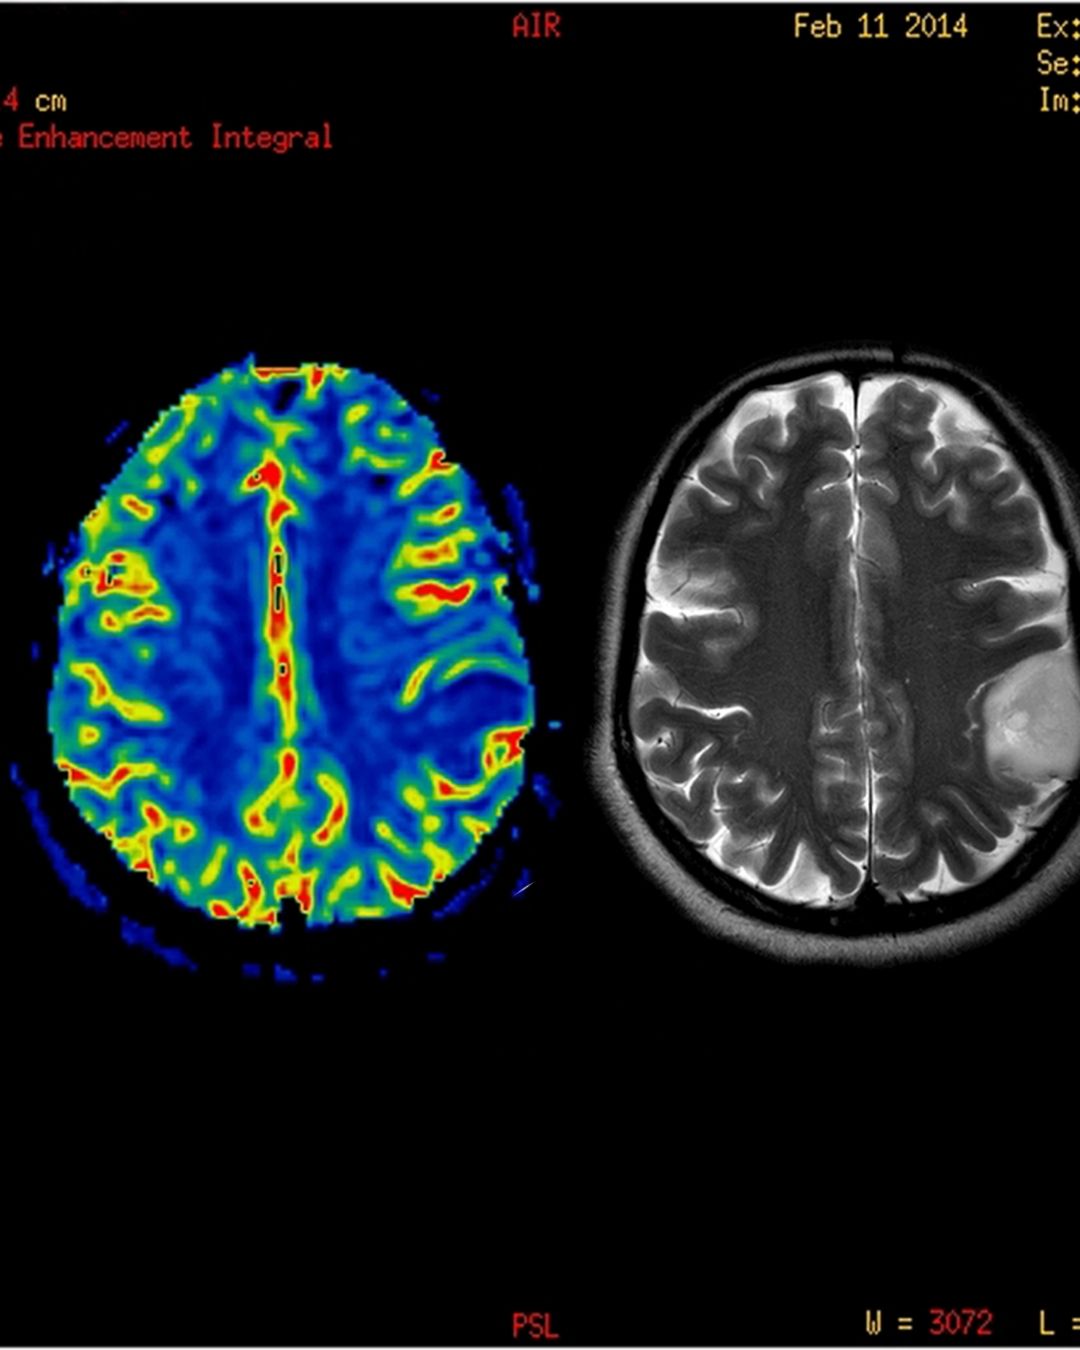

Perfüzyon MR (Manyetik Rezonans Perfüzyon), manyetik rezonans görüntüleme (MR) yönteminin bir türüdür ve dokuların kan akışını değerlendirmek için kullanılır. Özellikle beyin, kalp ve bazı tümörlerin kanlanmasının incelenmesinde yaygındır.

Bu yöntemde, damardan verilen kontrast maddesi veya kontrastsız teknikler kullanılarak, dokulara geçen kan miktarı ve kan akış hızı ölçülür. Böylece, dokuya ne kadar kan geldiği ve bunun zaman içindeki dağılımı görüntülenir.

• Beyin tümörlerinin kanlanmasının değerlendirilmesinde

Kısaca, Perfüzyon MR dokuların ne kadar iyi kanlandığını göstererek, hastalıkların tanısı ve tedavisinde önemli bilgiler sağlar.